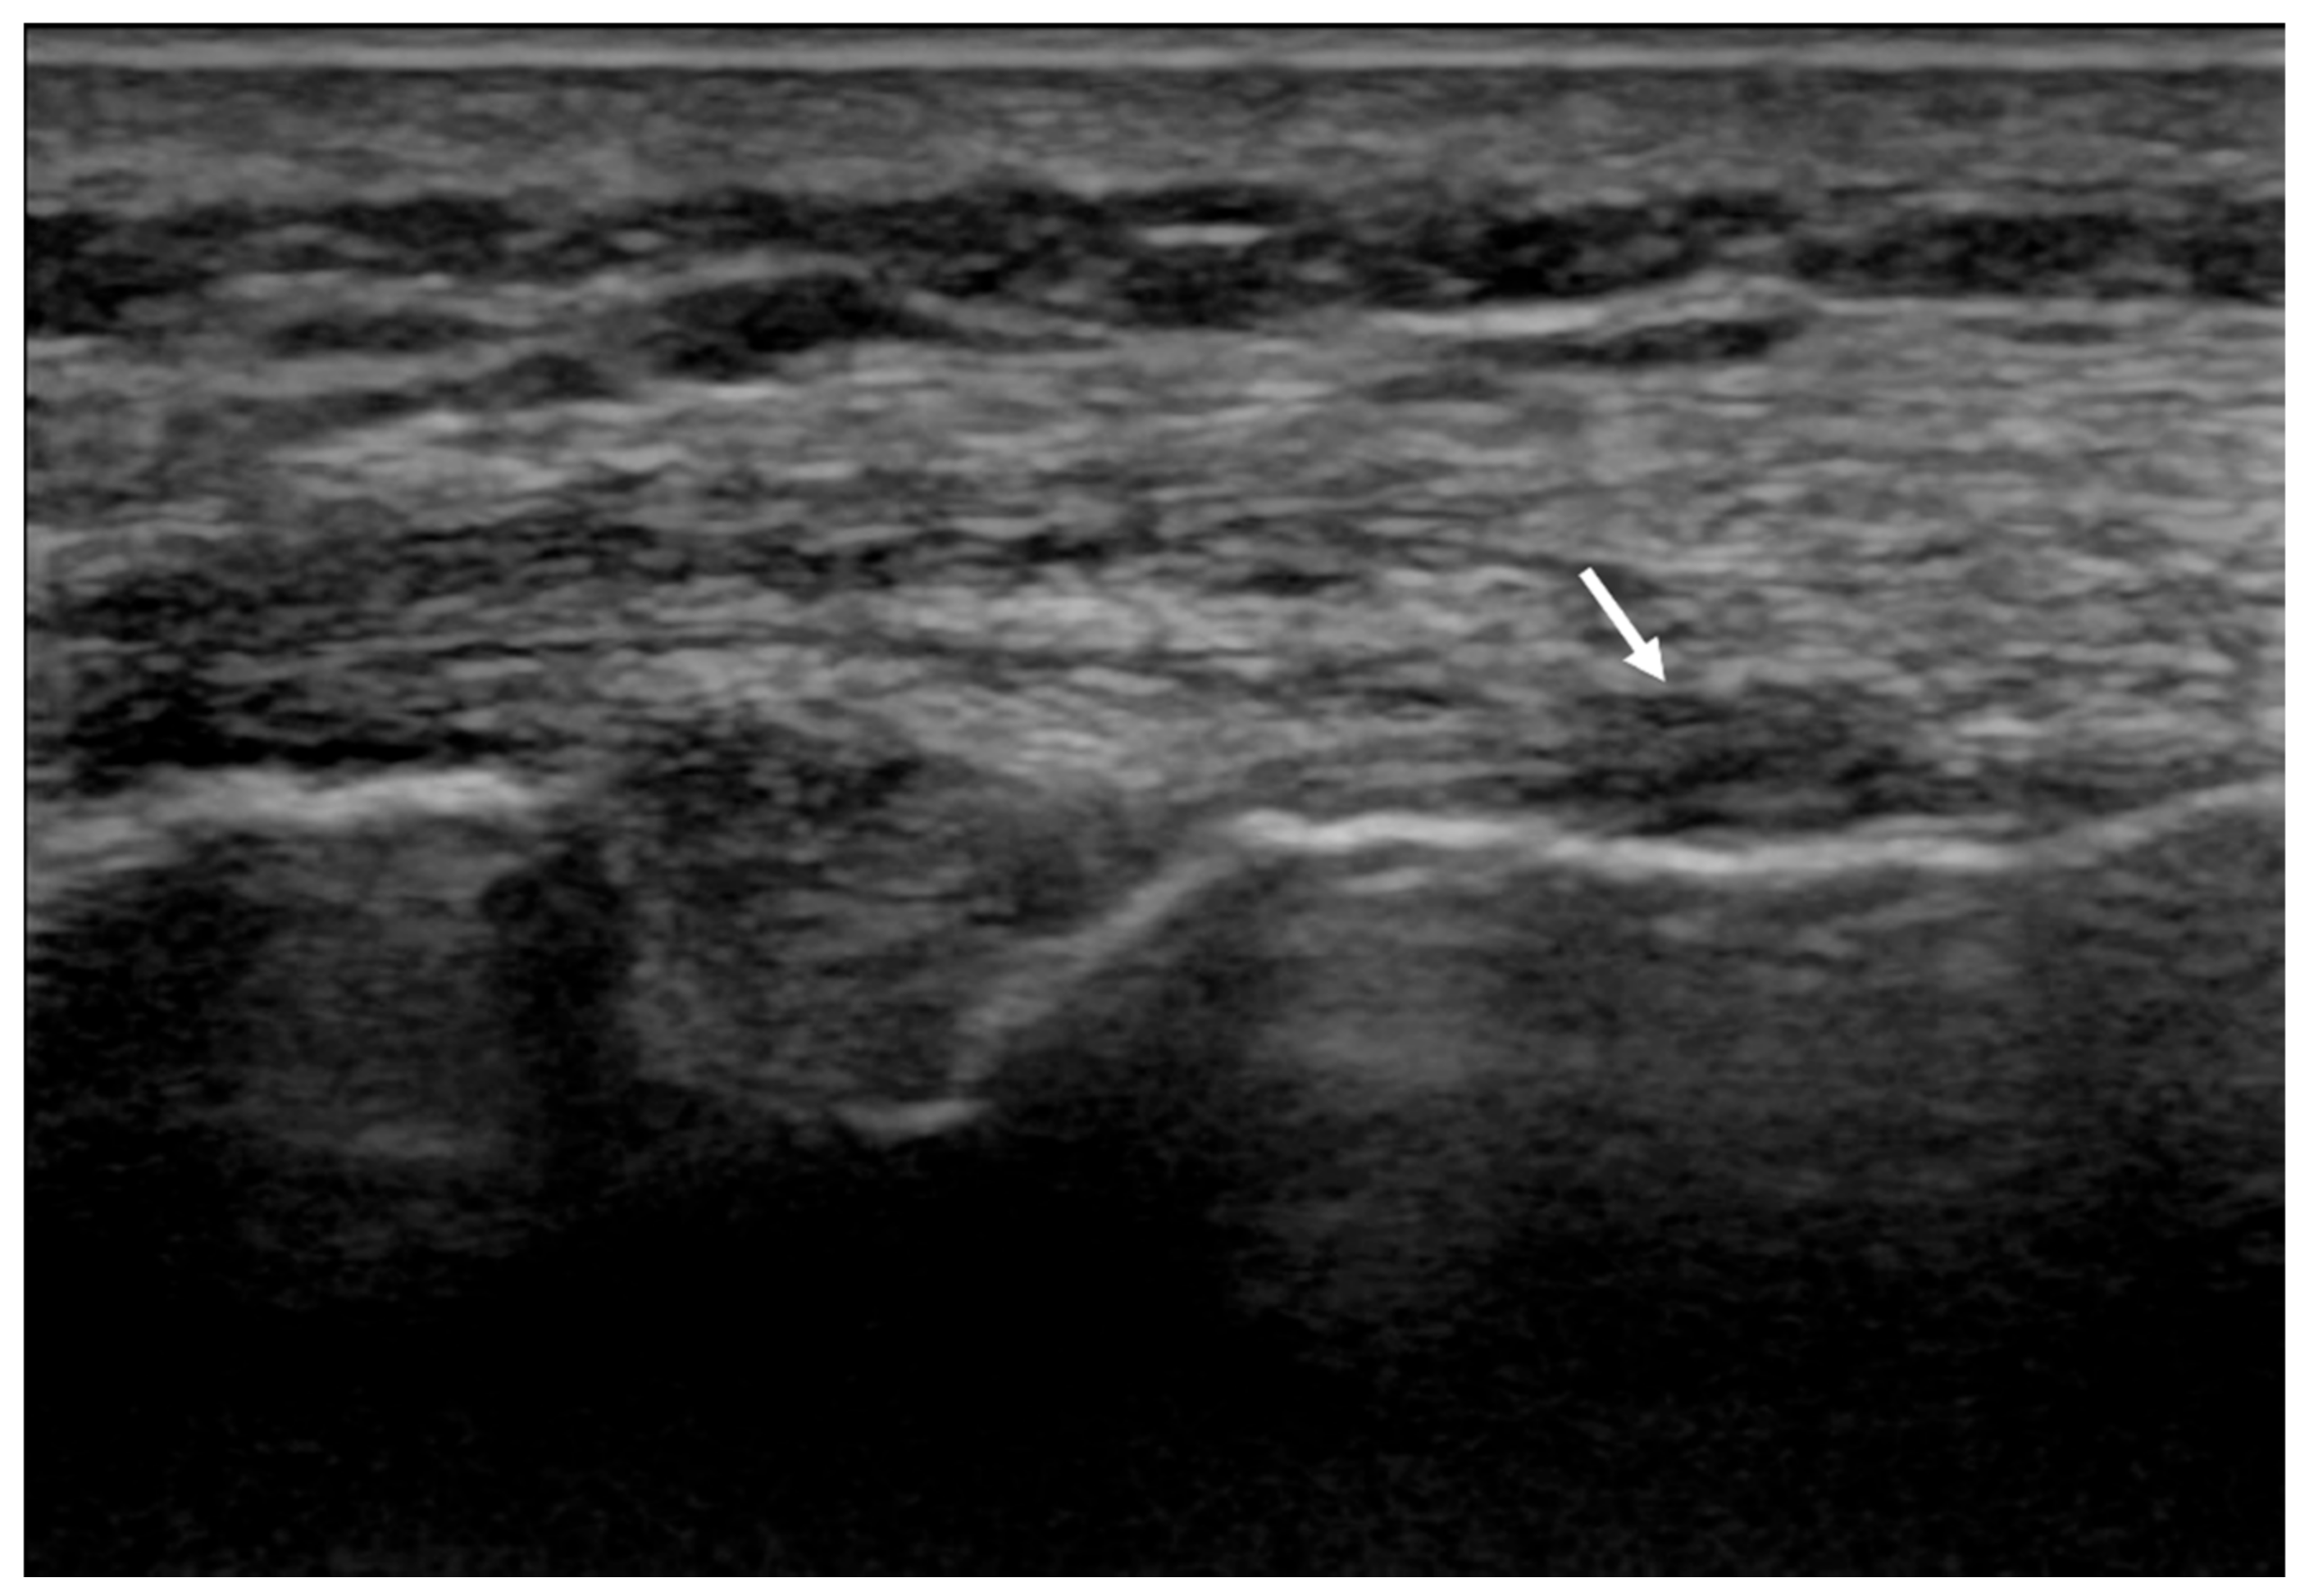

The clinical evaluation at 4 months post treatment revealed the continued complete absence of pain (VAS 0) with resumption of regular sports activities (walking, jogging) without any symptoms. Moreover, the US examination of the MCL showed a thinner ligament at the femoral insertion, with a clear improvement in echostructure (Figure 2).

Figure 2.

The 4-month follow-up ultrasound (US) examination of the MCL at the site of the previous injury (arrow).